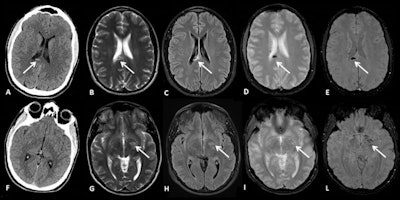

"Patients with high-energy trauma and a high risk of multisystemic involvement should generally be managed as polytrauma patients, and multidetector CT is currently the imaging technique of choice," they wrote. "MRI has a fundamental role in the evaluation of severe spine injuries before neurosurgical intervention and is the modality of choice for assessing the real extent of brain damage after severe head trauma."